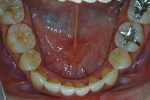

カテゴリー:ClassⅡ division 2 malocclusion (Overbite 5mm以上; 抜歯症例)

しかし、出題基準にも書いてあるように、このケースは欧米の白人によく見られるケースで、東洋人にはきわめて稀である。そこで類似ケースとして過蓋咬合(かがいこうごう)のケースを代替えとして認めるという配慮をしている。過蓋咬合とは非常に強く深く咬んでいる状態を言う。Overbiteとは前歯の垂直的な重なり具合を示す数値で、5mm以上だと上の前歯が下の前歯をほとんど覆い尽くしている感じになるので、前から見ると下の前歯はほとんど見えない状態になる。こういう状態が典型的な過蓋咬合である。典型的なclassⅡ,division 2のケースは過蓋咬合を合併している。

| 治療中